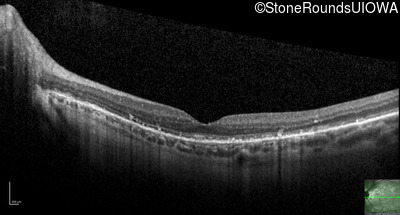

Optical Coherence Tomography - Right - 20/20 -1

Exemplar / OCT Stack

OCT Stack